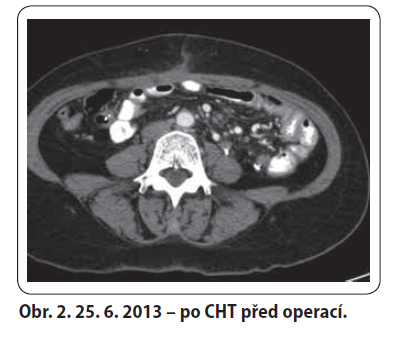

57letá žena, bez komorbidit a chronické medikace, došetřována od ledna 2012 pro chřipkové příznaky a váhový úbytek 10 kg. Proveden UZ břicha a gynekologické vyšetření s nálezem hypoechogenního útvaru v malé pánvi. Následně laparotomie s ovarektomií, kde v oblasti levé ovariální fosy tumor retroperitonea fi xující levý vaječník a vejcovod, potvrzeno i na CT. Histologicky dobře diferencovaný smíšený mezenchymální maligní tumor. 19. 7. 2012 v MOÚ Brno exstirpace nejasně ohraničeného tumoru (130 × 100 × 80 mm) spolu s hysterektomií. Histologicky high-grade polymorfocelulární sarkom bez bližší orgánové specifikace. Následně adjuvantní RT v KOC Zlín v dávce 46,8 Gy/ 26 fr. na malou pánev a 59,4 Gy/ 33 fr. na lůžko tumoru. Po ukončení RT pro bolesti zad provedeno CT. Na něm nově objemné expanzivní útvary mezi střevními kličkami a v levém mezogastriu – suspektní metastázy. V 1/ 2013 revize dutiny břišní v MOÚ Brno – nález inoperabilní, provedena paliativní spojková operace a vyvedena ileostomie. U pacientky s dobrým PS tedy indikována první linie paliativní CHT Adriamycin 3W. Od 2/ 2013 do 6/ 2013 bylo podáno celkem šest sérií se zajištěním filgrastimem pro neutropenie grade III. Dle CT přešetření bylo dosaženo parciální odpovědi. Z onkochirurgické komise KNTB pacientka indikována k operačnímu výkonu. 20. 8. 2013 byla provedena maximální debulking operace. Pooperačně CT i PET/ CT negativní. Poté podány tři série zajišťovací chemoterapie Adriamycin 3W s profylaktickým podáním filgrastimu. Kontrolní CT bez známek recidivy tumoru. V 3/ 2014 zanoření ileostomie. Dle CT restagingu z 5/ 2014 a 11/ 2014 trvá kompletní odpověď.